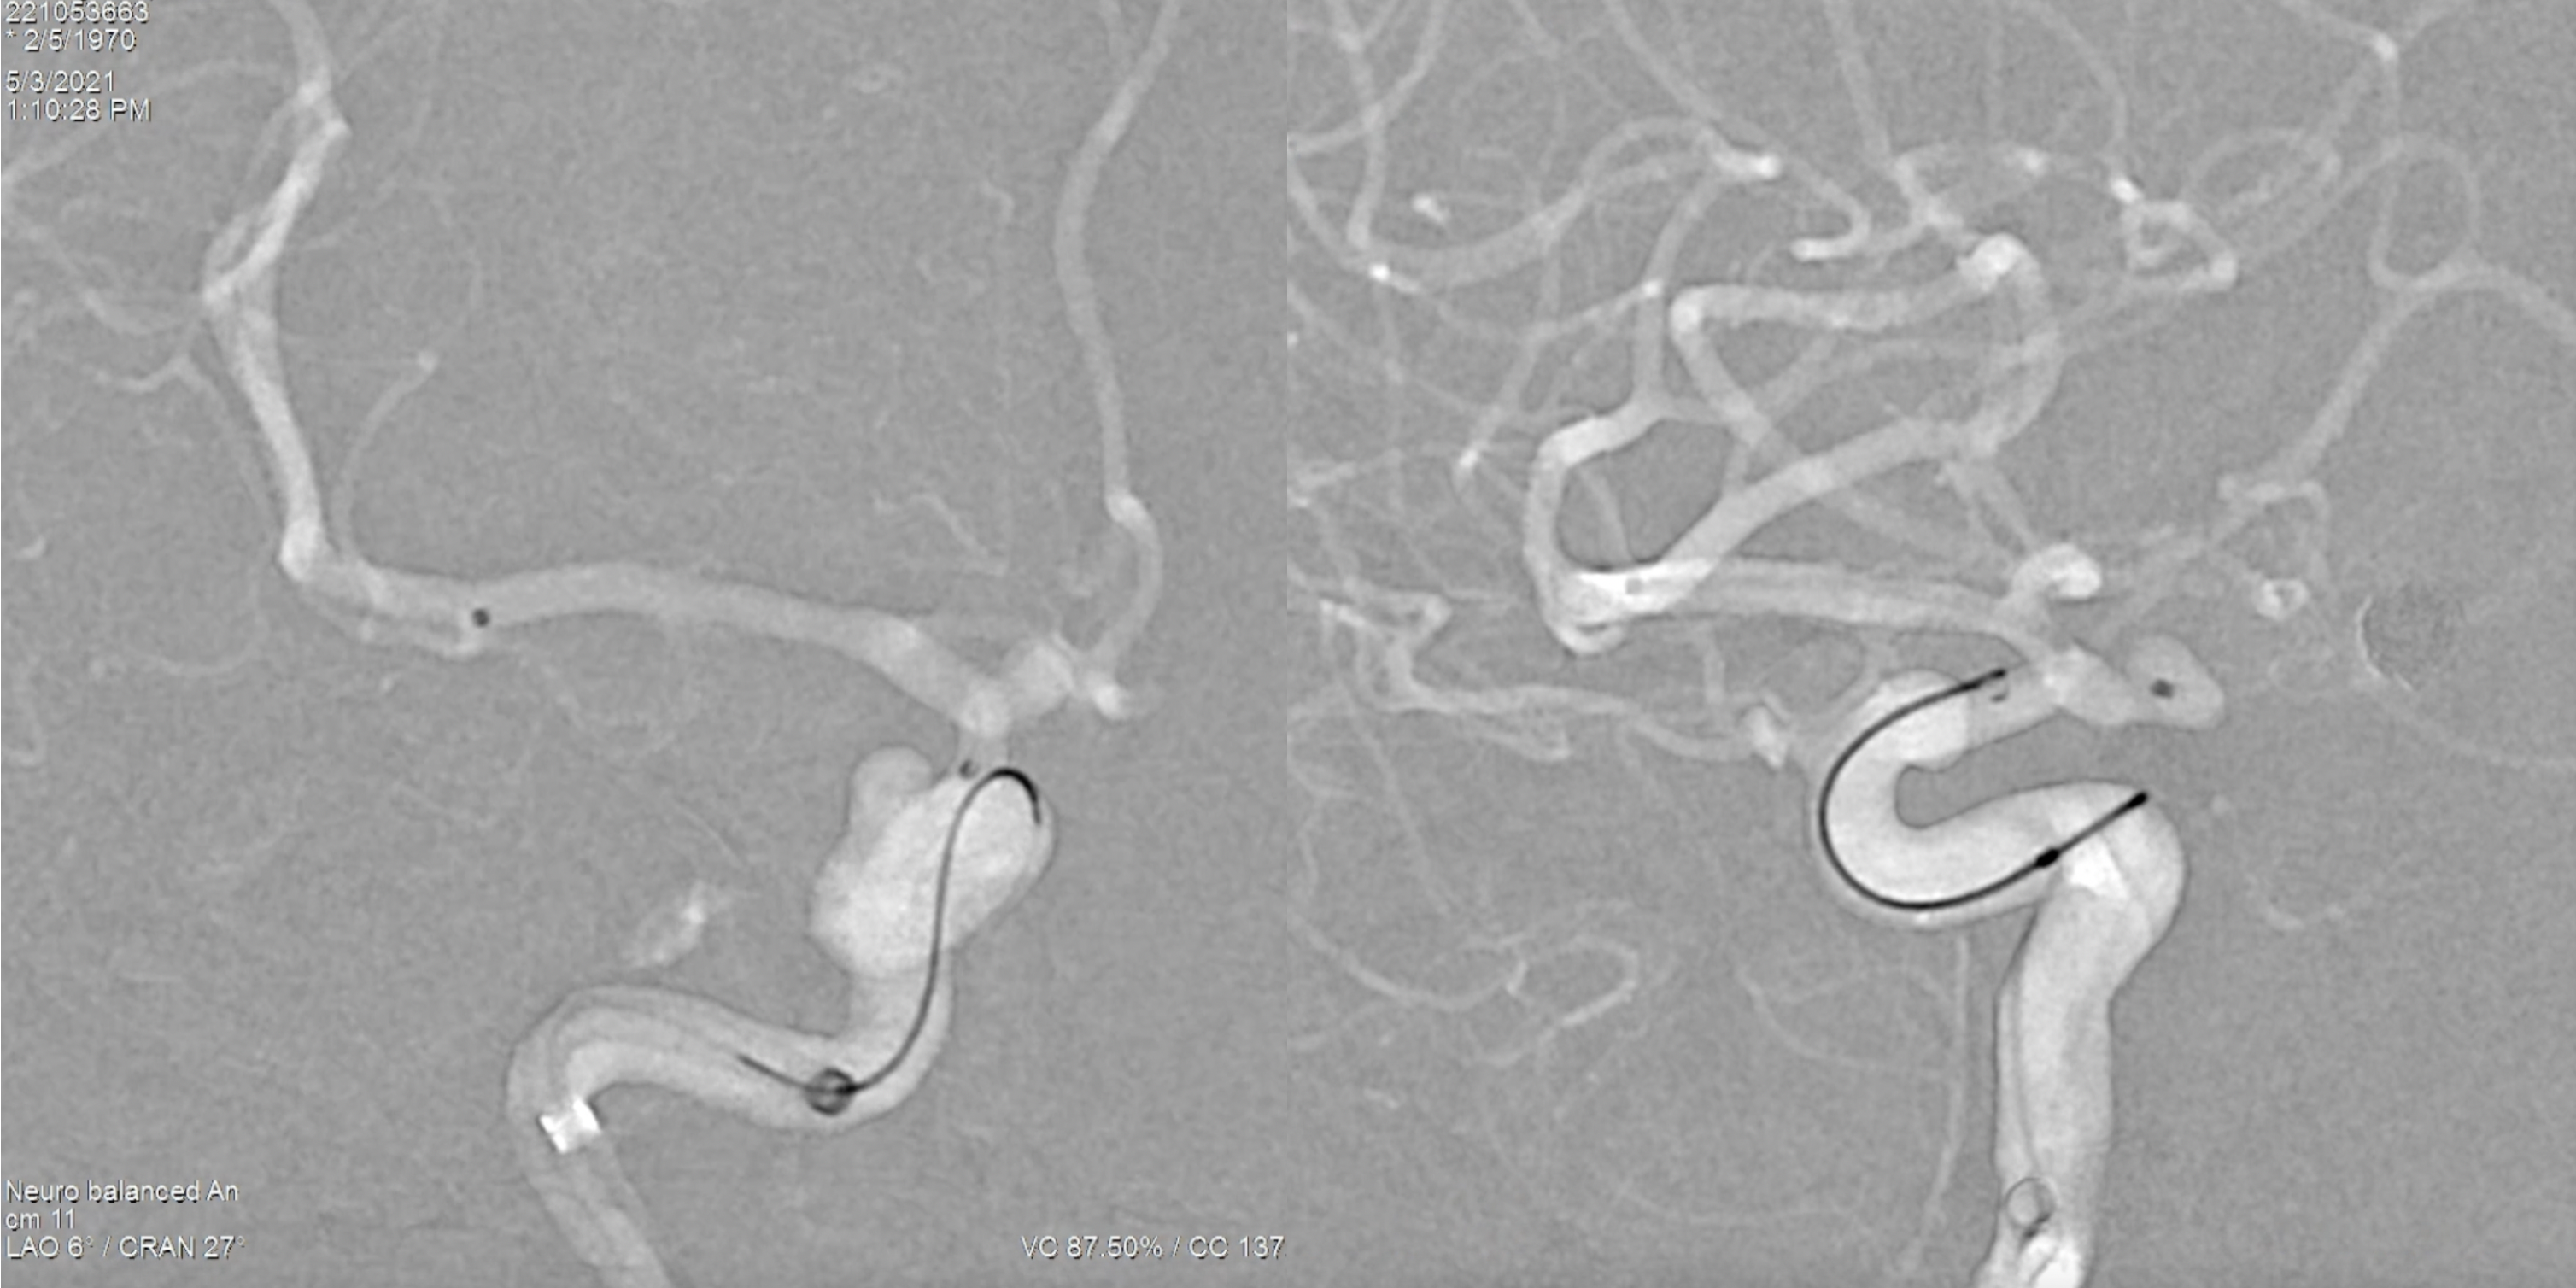

术后右侧颈内动脉正侧位造影:动脉瘤栓塞完全!

术后三维旋转造影:动脉瘤栓塞完全!